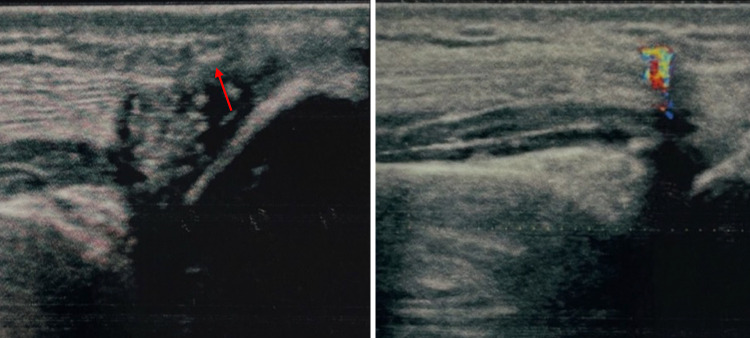

Fig. 2.

Case 2. A 25-year-old man was admitted to our hospital with a splinter of glass in the subcutaneous area of the palmar surface of the right hand. The splinter was barely visible on US grayscale as a small plaque of about 4 mm maximum size. In this case TA confirmed the presence and location of the FB

Fig. 3.

Case 3. A 36-year-old man was admitted to our hospital with a piece of metal in the muscle of the left arm. The FB was difficult to detect at US grayscale imaging but clearly visible at CDUS thanks to the presence of TA